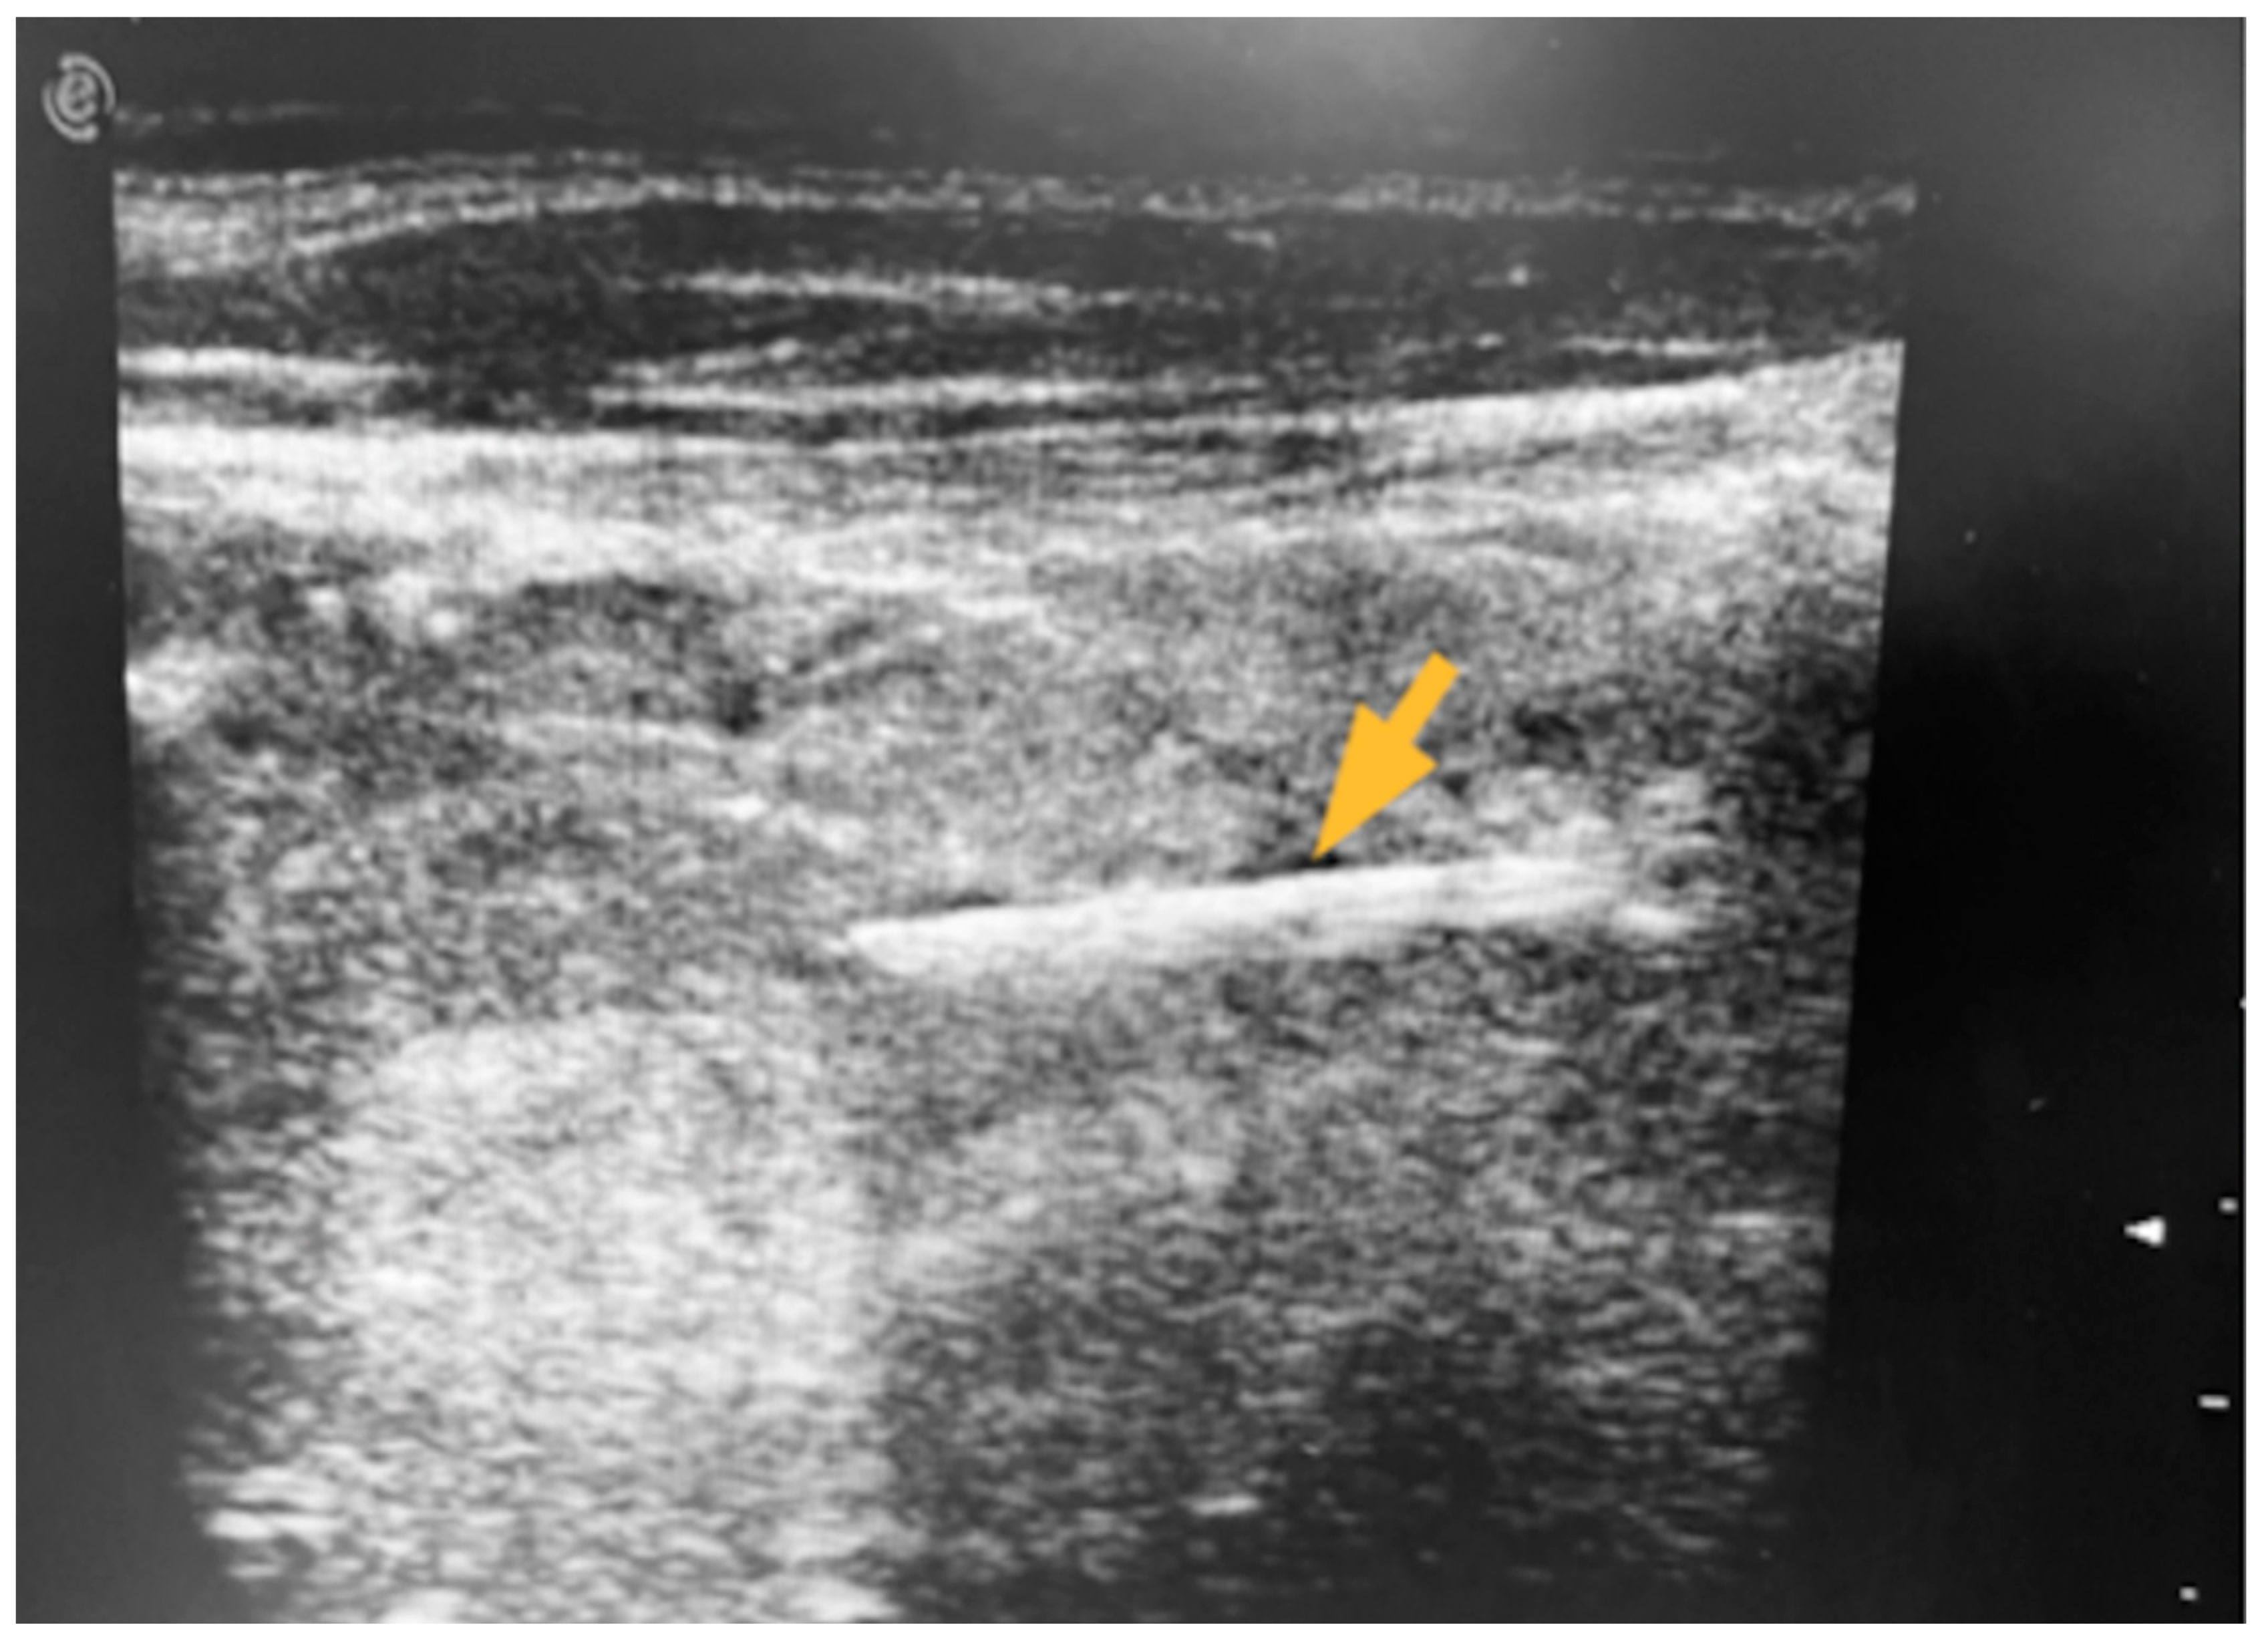

Figure 2.

Intraoperative US: the FB was detected as a hyperechoic line with a mild posterior hypoechoic halo (arrow).